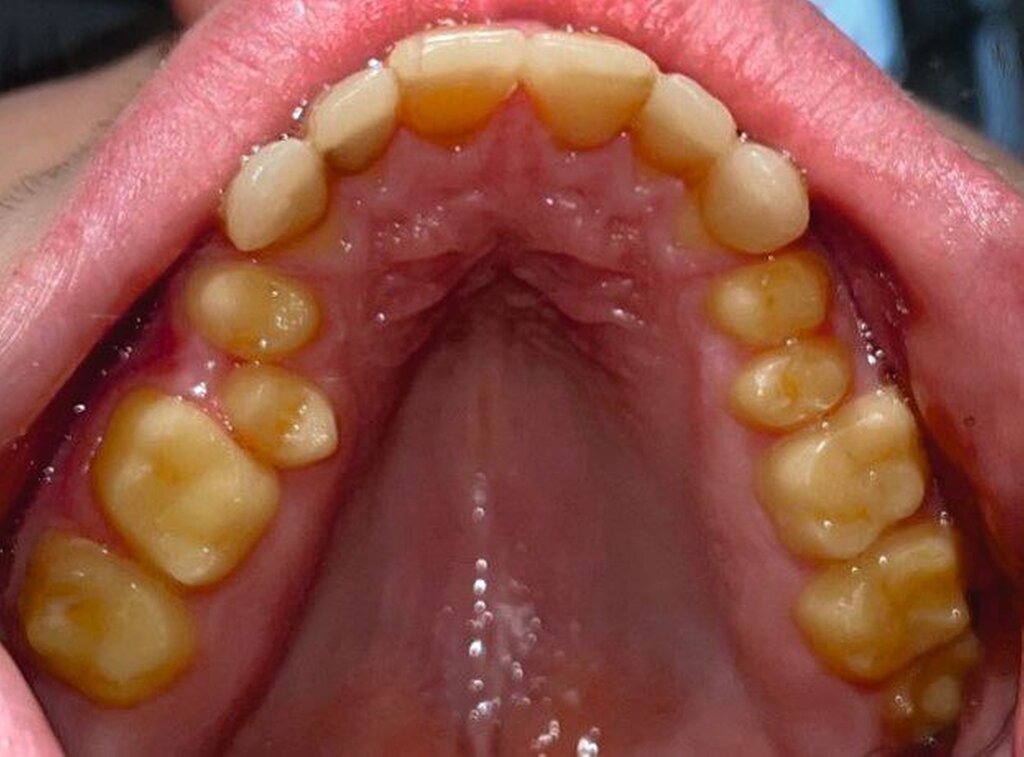

Klinisch zeigten sich ein nicht-kariöses Wechselgebiss mit generalisierter Schmelzhypoplasie an allen Zähnen sowie eine insuffiziente Mundhygiene. Zusätzlich bestanden eine fehlende Mittellinienübereinstimmung, ein Overbite von minus vier Millimetern und ein Overjet von sechs Millimetern (Abbildung 5), die sich phonetisch in einem interdentalen Sigmatismus äußerten. Röntgenologisch waren alle Zähne angelegt, jedoch war der Zahnschmelz stark reduziert oder vollständig fehlend (Abbildung 6).